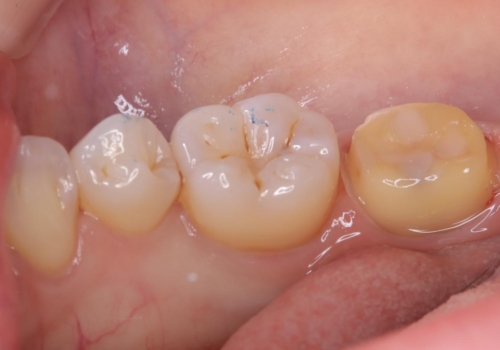

左下7頬側歯頚部に大きくできたう窩内のう蝕を除去していき、生活歯髄療法(間接覆髄法)を行いました。

二か月程期間を開け症状が出ていないことと、歯髄診断を再度行い正常反応を確認した後、セラミッククラウン補綴修復を行いました。